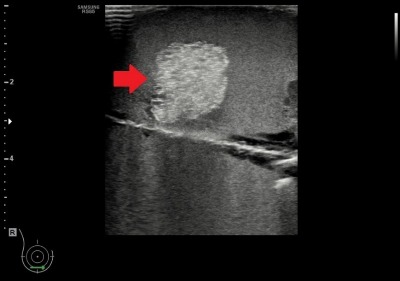

| ที่มา ข้อมูลเบื้องต้น ความสำคัญของปัญหา มะเร็งเต้านมเป็นมะเร็งที่พบบ่อยที่สุดในผู้หญิงไทยและมีแนวโน้มเพิ่มขึ้นต่อเนื่อง การตรวจคัดกรองจึงจำเป็น เพราะหากพบเร็วจะรักษาได้ทันและมีโอกาสหายสูง การใช้แมมโมแกรมร่วมกับอัลตราซาวด์ช่วยเพิ่มโอกาสพบรอยโรค ซึ่งต้องยืนยันด้วยการตรวจชิ้นเนื้อโดยใช้เครื่องมือทางรังสีช่วยนำเข็ม เนื่องจากรอยโรคมักคลำไม่พบ การฝึกใช้เครื่องมืออย่างมีประสิทธิภาพช่วยเพิ่มทักษะให้บุคลากรทางการแพทย์ จึงมีการพัฒนาเต้านมจำลองสำหรับฝึกนำเข็มอัลตราซาวด์เก็บชิ้นเนื้อ ซึ่งควรมีลักษณะเหมือนเต้านมจริง เห็นก้อนและเข็มชัด ใช้ซ้ำได้ ไม่ทิ้งรอยเข็ม และมีราคาที่เหมาะสม เทคโนโลยีทางด้านวัสดุเลียนแบบเนื้อเยื่อที่สามารถซ่อมแซมตัวเองได้ที่พัฒนามาใช้ในการทำเต้านมจำลองนี้ ได้ถูกพัฒนาต่อยอดร่วมกับเทคนิคการขึ้นรูป จึงสามารถพัฒนาอวัยวะอื่น ๆ เพื่อฝึกทำหัตถการ เช่น ผิวหนังเทียมในการฝึกเย็บ หรือตับที่สามารถแสดงภาพอัลตราซาวด์โดยที่มีรายละเอียดของเส้นเลือดหรือท่อน้ำดีเพื่อใช้ฝึกวินิจฉัย เป็นต้น |

| สรุปเทคโนโลยี • ให้ภาพอัลตราซาวด์ที่เห็นก้อนเนื้อชนิดต่าง ๆ ชัดเจน • ให้ภาพอัลตราซาวด์ของเข็มเจาะชัดเจน • สามารถใช้ซ้ำเนื่องจากวัสดุมีคุณสมบัติซ่อมแซมตัวเองได้ • สามารถต่อยอดไปสู่การพัฒนาอวัยวะอื่น ๆ เพื่อให้แพทย์ได้ฝึกทำหัตถการ |